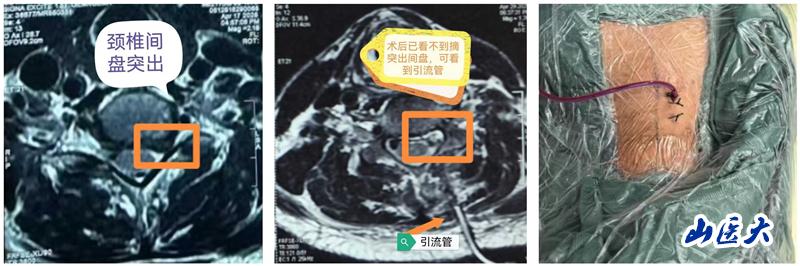

近日,我校第二医院骨科脊柱二病区王少伟教授团队成功为一例神经根型颈椎病患者实施了单侧双通道内镜下的颈椎Keyhole(俗称“钥匙孔”)微创手术。手术全程顺利,术中精准解除患者神经压迫,术后患者左上肢疼痛即刻解除,术后第二天便可下床正常行走。

颈椎Keyhole微创手术是指在椎板上开设一个如钥匙孔般精细的通道,通过脊柱内镜技术完成病灶清除与神经减压。该术式不仅最大程度地保留正常解剖结构,还能有效缓解神经根压迫,为颈椎疾病患者带来更加舒适的治疗体验和更快的康复进程。近年来,随着脊柱内镜技术的迅猛发展,单侧双通道内镜技术在腰椎疾病的治疗中得到了广泛应用,如今,这项先进技术正逐步延伸至颈椎领域,开启了颈椎治疗的全新篇章。作为一项突破性的微创治疗手段,Keyhole入路为神经根型颈椎病的手术治疗提供了更安全、更精准、更高效的解决方案。